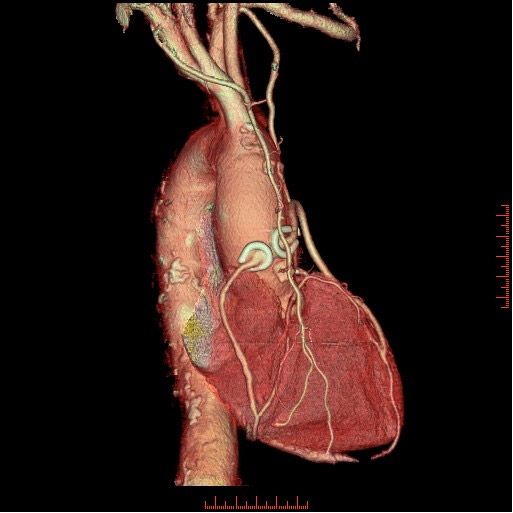

冠状動脈バイパス手術後の経過観

手術後の患者様の経過を下記の通り観察できます。心臓の裏側ももちろん診断可能です。

様々な画像表示処理方法を用い診断します。

ボリュームレンダリング